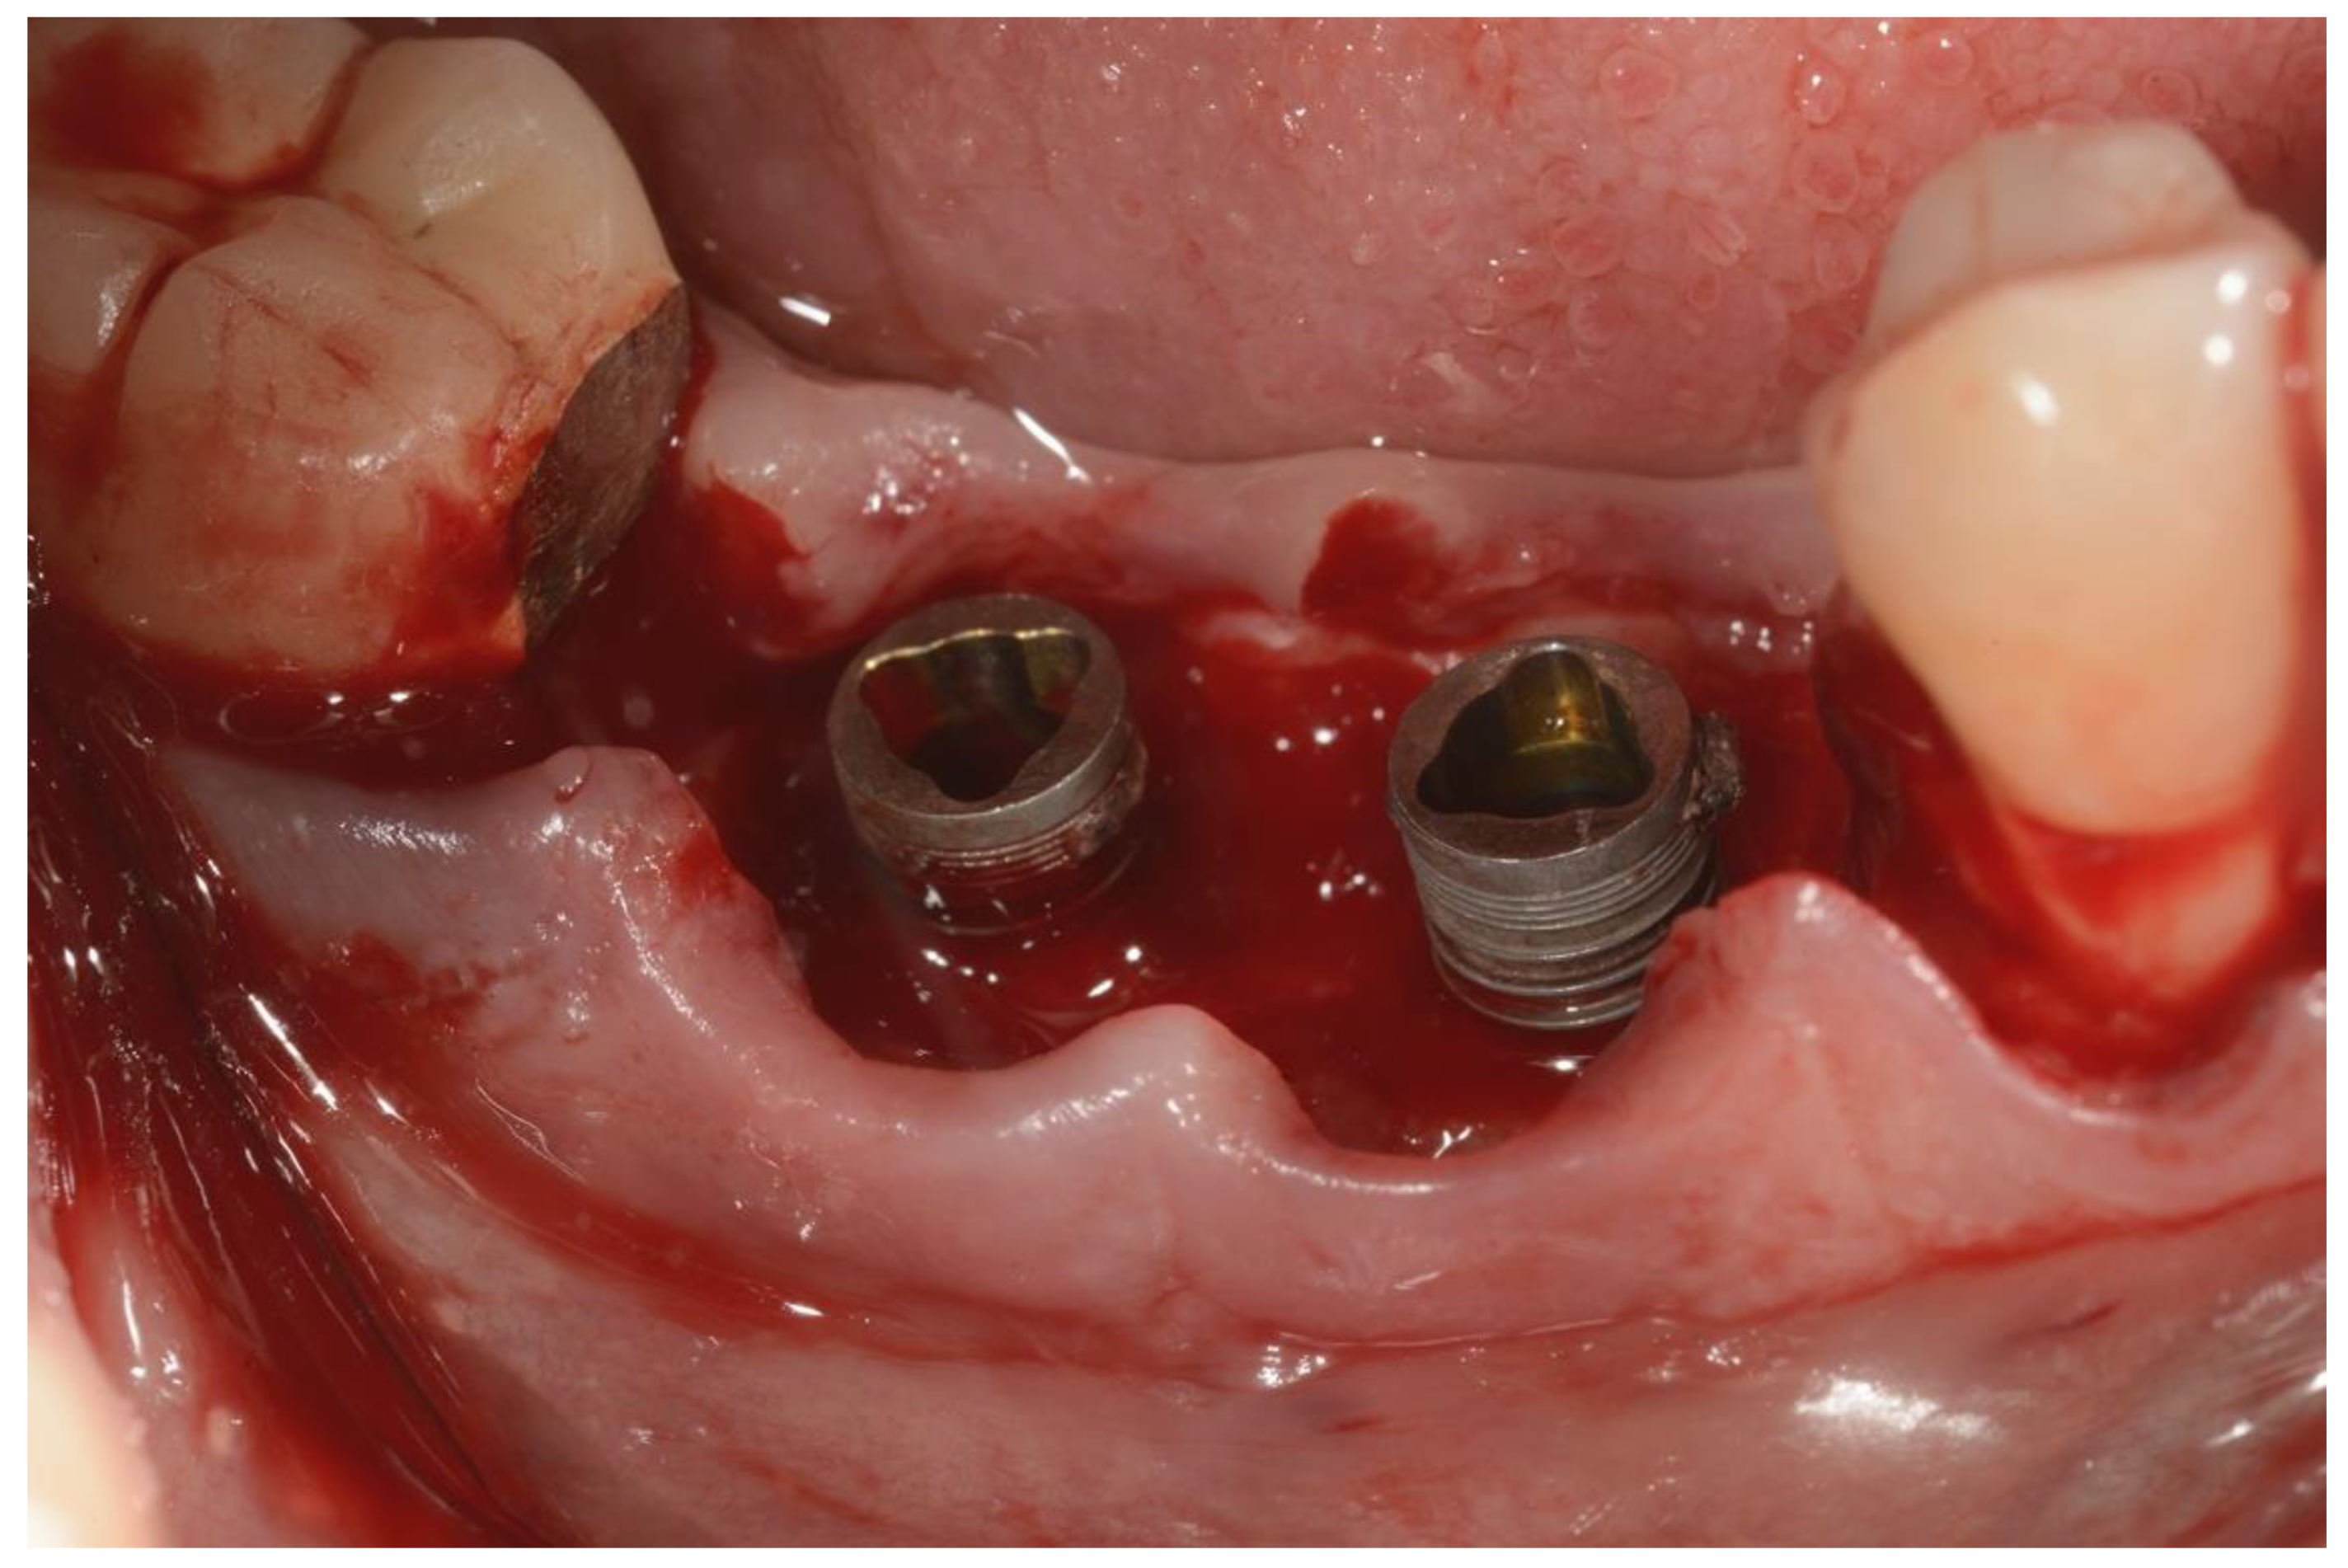

Peri-Implantitis: Application of a Protocol for the Regeneration of Deep Osseous Defects. A Retrospective Case Series

2. Materials and Methods